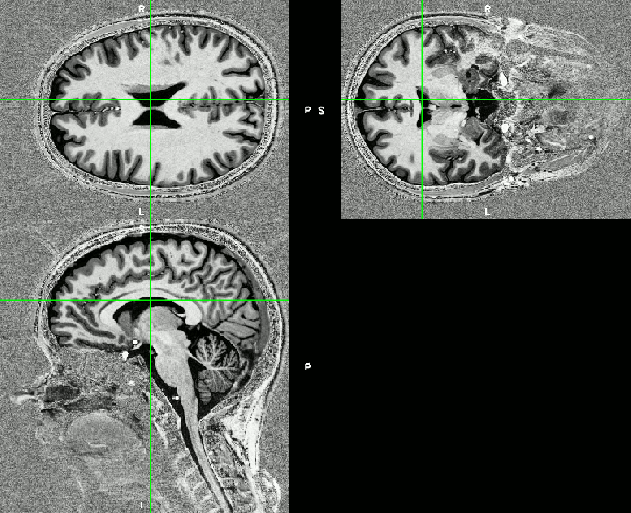

In layer-fMRI, it is common to use very high-resolution anatomical reference data with resolutions in the range of isotropic 0.35-0.6 mm. Since it would 30-60 min to acquire a whole brain dataset at this resolutions, it is customary to acquire a local slab of the high-res data only. With appropriate GRAPPA acceleration, such a high-resolution slab can be acquired in 2-4 min. For high SNR, however, it is helpful to acquire 2-3 repetitions of such a slab and retrospectively align them and averaged them together. The big challenge of the noise amplification in non-brain areas is that the alignment algorithms can be affected by the background noise and do not perform with their best accuracy. Thus, it can be helpful to suppress the background noise with an additional regularization term during the complex division.

Foldover at slab data

Almost all layer-fMRI studies are focusing on specific cortical areas only and do not require whole brain coverage. Thus, there is no need to acquire the high-resolution anatomical reference data for the whole brain either. This would result in impractically long acquisition times. Instead, it is beneficial to use a slab-selective 3D-acquisition approach. With the default parameters of the SIEMENS MP2RAGE sequence, however, this can result in severe fold-over artifacts that render up to 45% of the slices unusable (see gif animations below).

With a bit of tweaking and almost no hit in SNR, the usable number of slices can be substantially increased.

The default excitation pulse of the SIEMENS MP2RAGE sequence has a Bandwidth-Time-Product (BWTP) of 6.4. Which means that the excitation profile is not super sharp. By changing the RF-mode in the sequence special card from Fast to Normal, the BWTP is doubled to 12.7.

The only (negligible) drawback is that the SAR inceases by 0.5-1.5% and that the minimal TR increases by 1 ms. Pushing the BWTP even further to 25, would reduce the fold over artifact even further (shown in fig below).